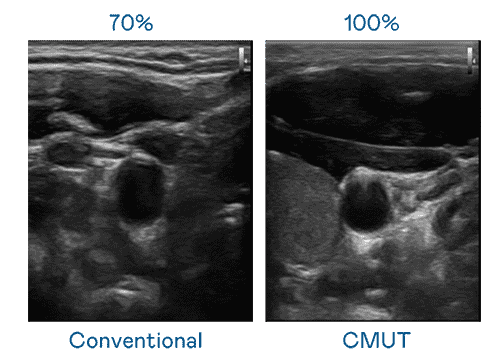

CMUT 技术是一种用电容式微机电元件来产生超音波讯号的技术。。。与传统 PZT 压电式技术相比,,,CMUT 频宽增加 30%,,,,更宽频的超音波讯号让影像解析度大幅提升,,是实现高影像品质医疗超音波扫描、、、、促进精准医疗发展的关键技术。。

大频宽带来超清晰影像

超音波影像的解析度高低,,,首先取决于探头能发出的讯号频宽。。。Wepay CMUT 可提供高清晰的超音波讯号,,提供高频宽、、、高灵敏度、、、、影像纹理细节更高的超音波影像,,协助医护人员缩短影像判读时间及利用精准的医疗影像进行诊断。。。。